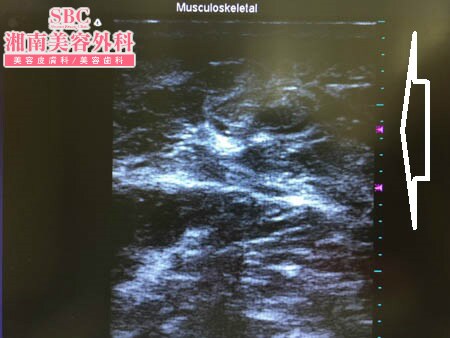

No.151007【脂肪吸引】ハワイからご来院!!圧倒的吸引量で圧倒的満足度!あの有名な根こそぎ竹田先生の劇的ビフォーアフター!〜左二の腕術中3Dタッチビュー〜

もちろん皮下脂肪の取り残しを避けるために

3Dタッチビューを用いて

ターゲットとなる皮下脂肪層をチェックします。

右の二の腕の手術直前と直後の状態を

画像で見てみましょう。